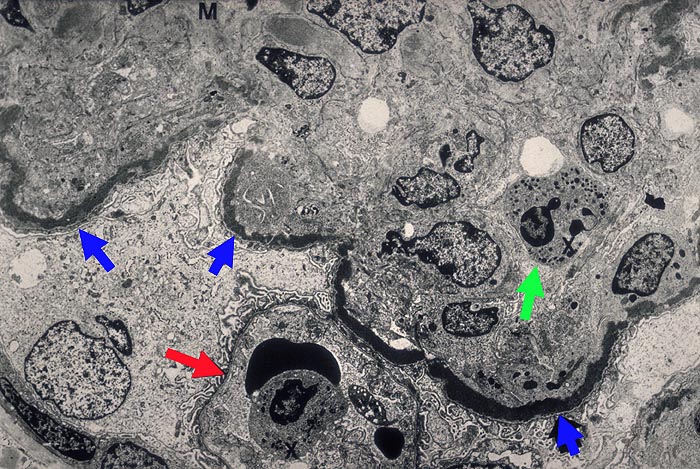

Dense deposit disease: intramembranöse Glomerulonephritis

Eine der Schlingen weist keine osmiophilen Depots auf. In der benachbarten Schlinge massive, bandförmige Depots. In den Schlingenlumina findet man neutrophile Granulozyten, daneben auch Monozyten. Im Mesangium besteht eine deutliche Sklerose, begleitet von einzelnen osmiophilen Depots.

Im EM: intramembranöse stark osmiophile bandförmige Depots auch in der Bowman'Kapselbasalmembran, Arteriolen und tubulären Basalmembranen. DD: Leichtketten Nephropathie.